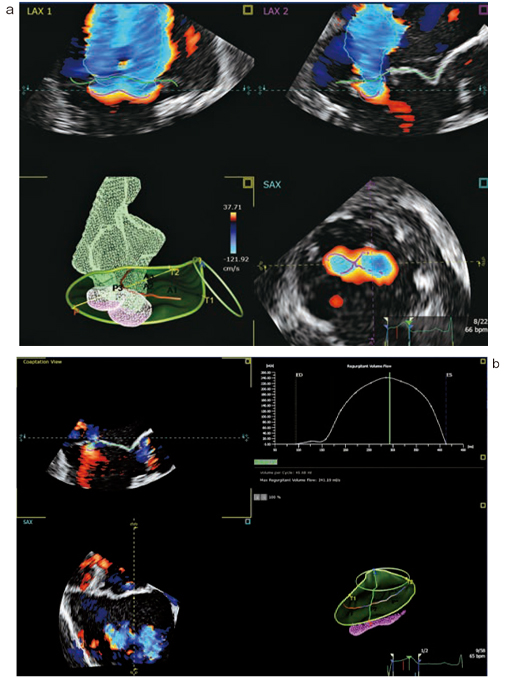

原理は,まず,取り込まれた3Dカラードプラの情報から,AIが自動的に吸い込みの表面積を認識する。次に,吸い込みの位置と形からMRジェットの形を計算する(図3 a)。計算されたMRジェットと実際のMRジェットを比較して,吸い込みの位置や形を修正し,さらに,MRジェットを再計算する。これを繰り返して精度を高め,最終的に得られた吸い込みの3Dの表面積と吸い込みの流速から,瞬間のMR volume rateを算出し,それを収縮期の全時相で積分し,MR volumeを算出する(図3 b)。

吸い込みの表面積を3Dで,しかも,収縮期の全時相で認識することで,より精度の高いMR volumeが算出可能となった。すでに論文が報告されており,心臓MRI(CMR)とよい相関があることが示されている3)。

図3 3D Auto CFQ

a:吸い込みの位置と形からMRジェットの形を計算し,実際のMRジェットと比較している。

b:得られた吸い込みの3Dの表面積と吸い込みの流速から,瞬間のMR volume rateを算出し,それを収縮期の全時相で積分し,MR volumeを算出する。